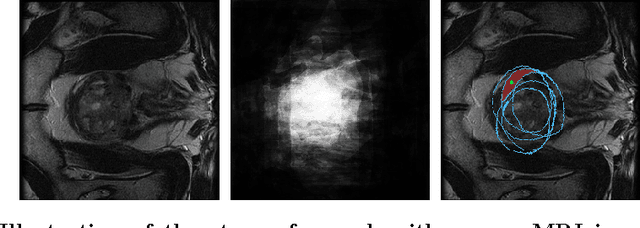

Abstract:We propose a novel hands-free method to interactively segment 3D medical volumes. In our scenario, a human user progressively segments an organ by answering a series of questions of the form "Is this voxel inside the object to segment?". At each iteration, the chosen question is defined as the one halving a set of candidate segmentations given the answered questions. For a quick and efficient exploration, these segmentations are sampled according to the Metropolis-Hastings algorithm. Our sampling technique relies on a combination of relaxed shape prior, learnt probability map and consistency with previous answers. We demonstrate the potential of our strategy on a prostate segmentation MRI dataset. Through the study of failure cases with synthetic examples, we demonstrate the adaptation potential of our method. We also show that our method outperforms two intuitive baselines: one based on random questions, the other one being the thresholded probability map.